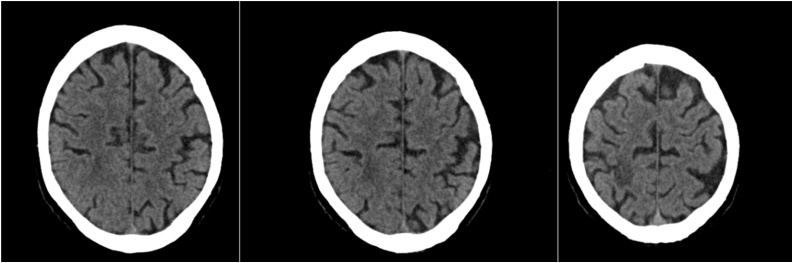

Follow-up contrast CCT after seven weeks revealed marked BA and perifocal edema reduction. Antibiotic therapy was further continued to realize total resolution of the BA to enable HTX in this patient with PET-CT proven LVAD system infection and finally after thirteen weeks of antibiotic treatment CCT in conclusion publicized complete resolution of the BA (Fig. 3).

Fig. 3.

CT Scan with contrast a complete regression of the lesion and the surrounding edema.

For optimal preparation for HTX the extent of the LVAD system infection was reassessed in PET-CT but surprisingly after thirteen weeks of broad-spectrum antibiotic therapy no LVAD system infection was traceable in PET-CT anymore and the patient has not experienced clinical significant infection recurrence afterwards.